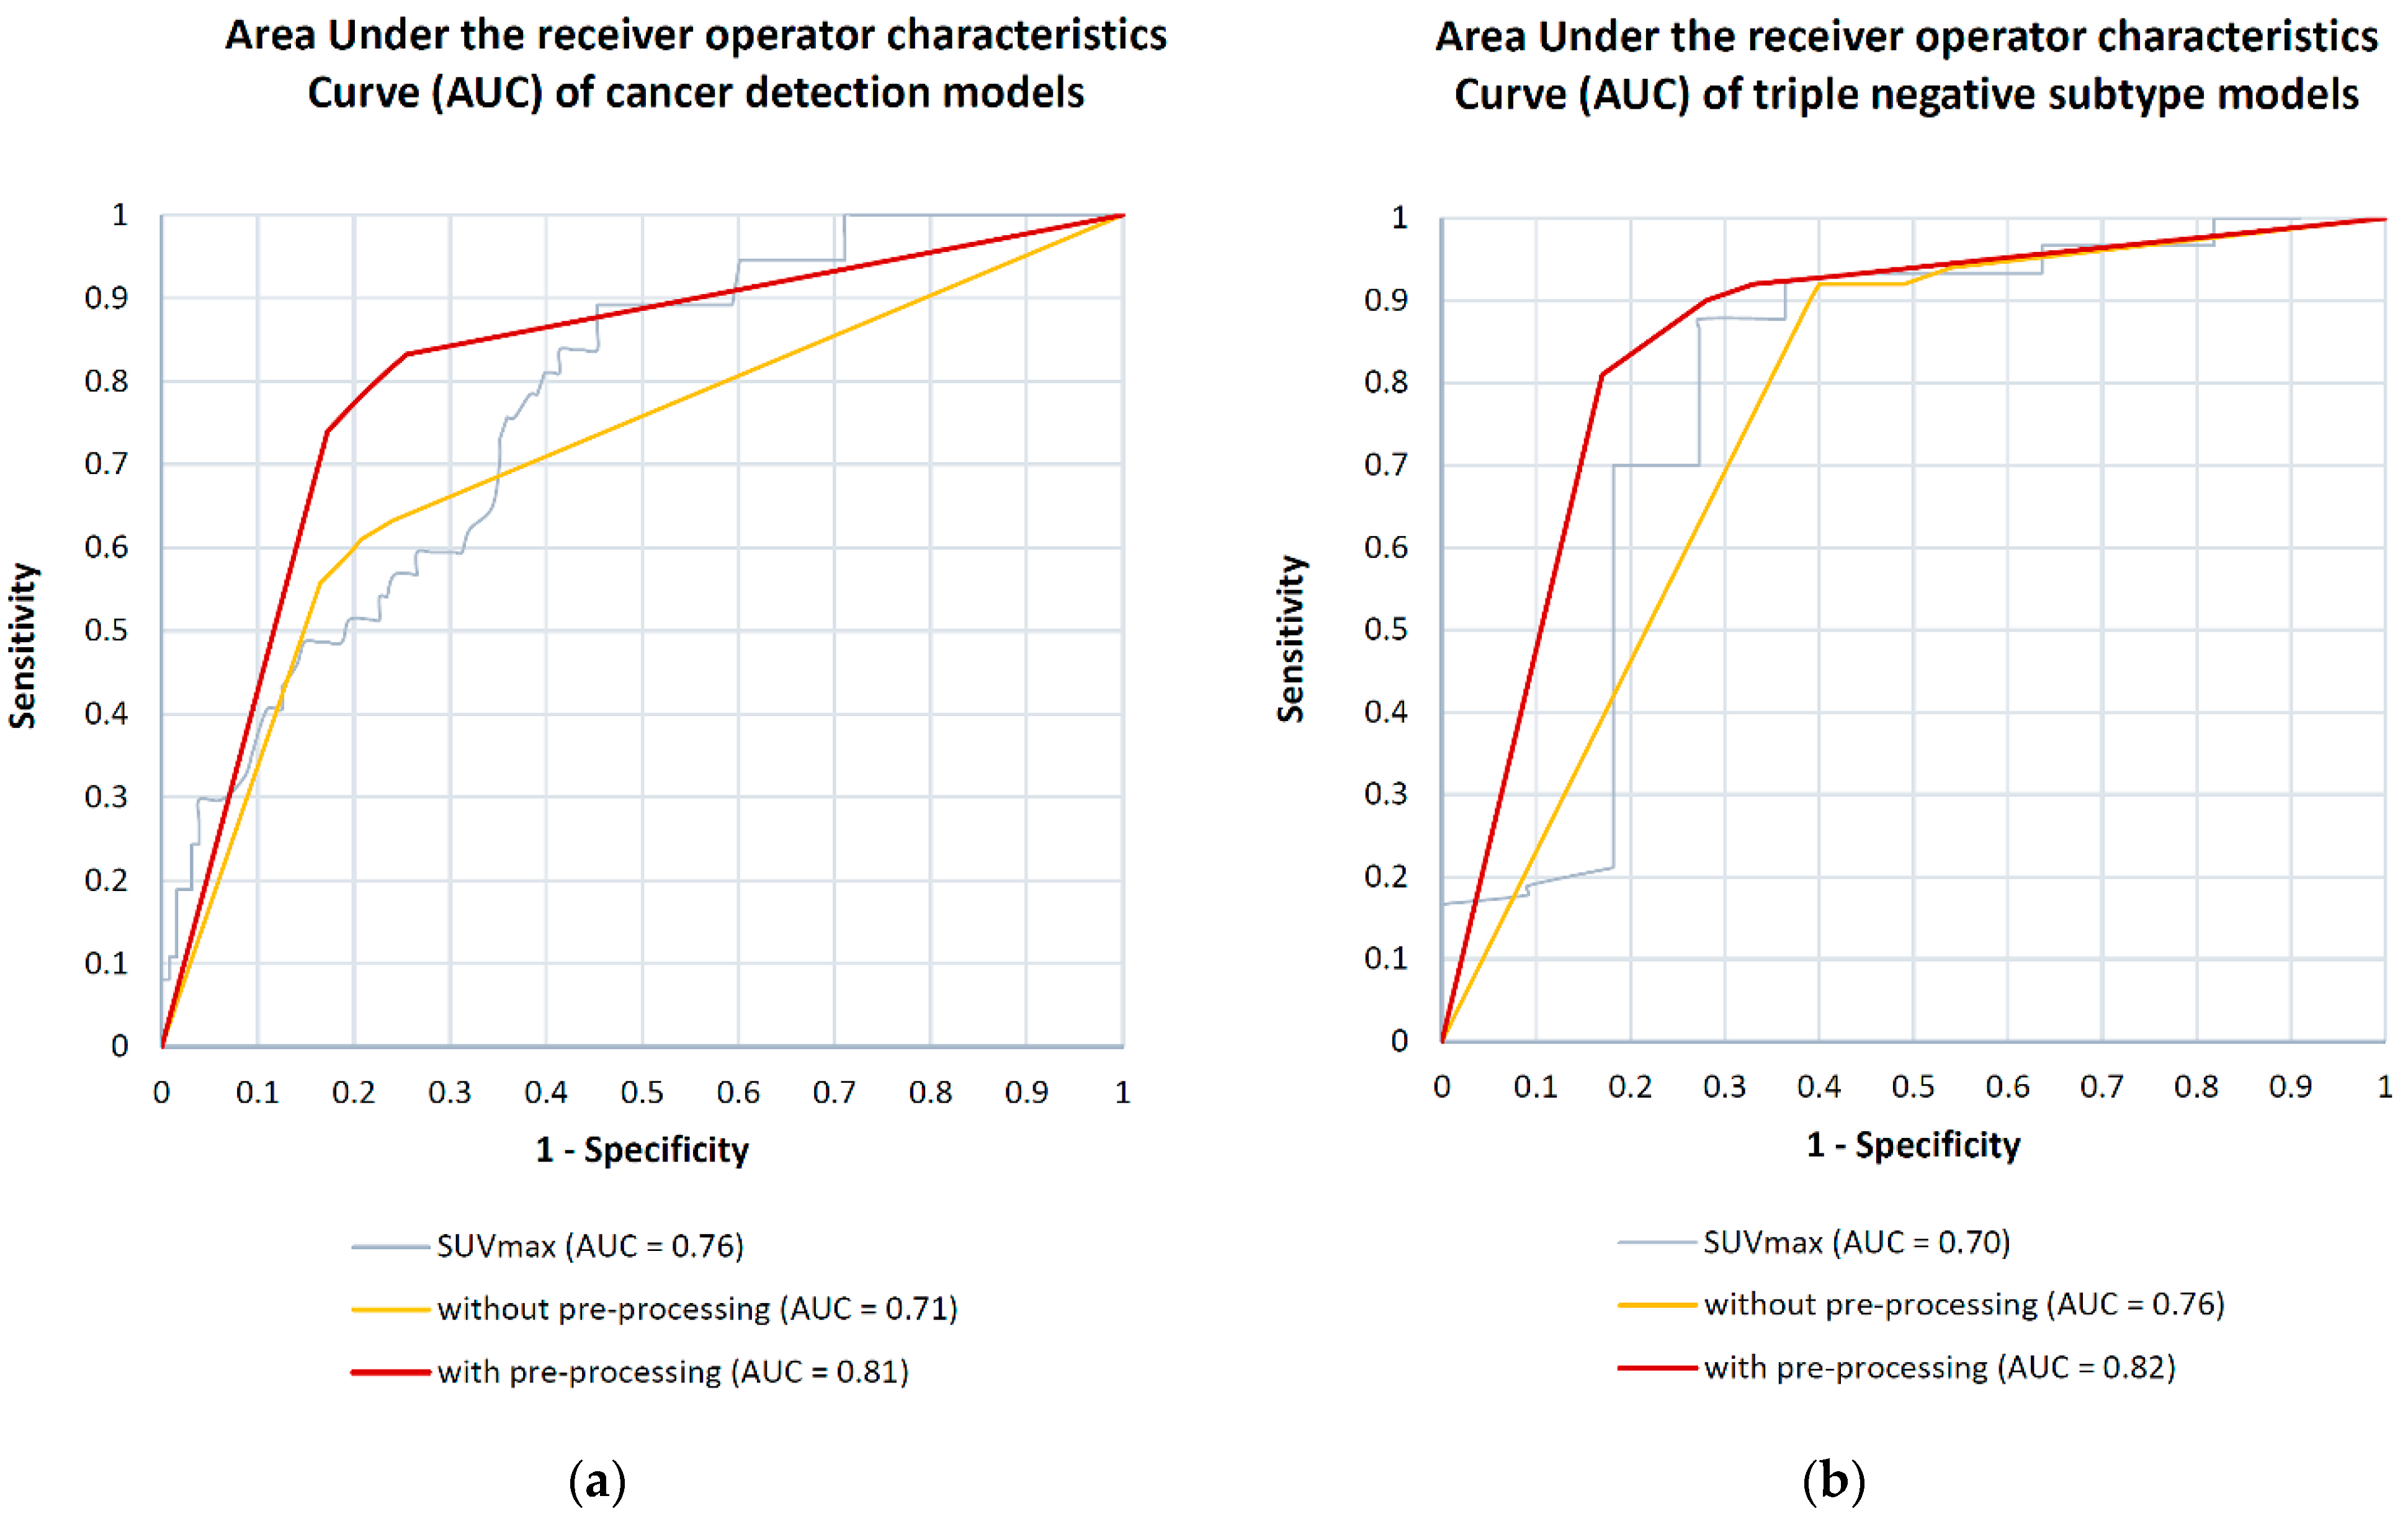

3.2.1. Breast Cancer Detection

3.2.2. Breast Cancer Subtyping

| Model | Data Preprocessing | SENS | SPEC | NPV | PPV | ACC | AUC |

|---|---|---|---|---|---|---|---|

| ER | No | 83 | 40 | 70 | 58 | 62 | 0.63 |

| Yes | 82 | 56↑ | 78↑ | 65↑ | 69↑ | 0.68↑ | |

| PR | No | 74 | 36 | 58 | 54 | 55 | 0.56 |

| Yes | 78↑ | 35 | 61↑ | 54 | 56↑ | 0.55 | |

| Ki-67 | No | 68 | 39 | 55 | 53 | 53 | 0.63 |

| Yes | 65 | 45↑ | 56↑ | 54↑ | 55↑ | 0.65↑ | |

| HER2 | No | 17 | 84 | 50 | 51 | 50 | 0.46 |

| Yes | 17 | 84 | 50 | 51 | 50 | 0.46 | |

| Luminal A/B | No | 17 | 87 | 51 | 57 | 52 | 0.62 |

| Yes | 16 | 89↑ | 51 | 59↑ | 53↑ | 0.52 | |

| Triple negative | No | 57 | 94 | 68 | 90 | 75 | 0.76 |

| Yes | 85↑ | 78 | 84↑ | 79 | 82↑ | 0.82↑ | |

| Breast Cancer Detection (Malignant vs. Benign) | No | 80 | 59 | 75 | 66 | 69 | 0.71 |

| Yes | 80 | 78↑ | 79↑ | 78↑ | 80↑ | 0.81↑ |